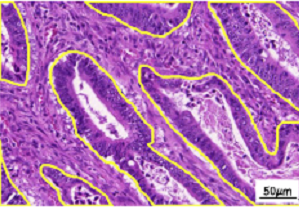

In the last few decades, the advent of computational pathology has catalyzed the advancements in clinical diagnosis, expedited development of new interactive models for pathology education and paved way for incredible rise in whole slide image analysis tools. It has revolutionized the entire tissue specimen analysis process for pathologists. From manually analyzing thousands of tissue slides via microscope requiring specialized doctors to automatic digital slide generation via scanning and using AI based deep learning techniques has spawned fatal disease diagnosis such as cancer using image analysis. In digital pathology nuclei and gland instance segmentation in whole slide images is of pivotal value for abnormality assessment. It plays a key role in histopathological image analyses whether it be identification of major chronic disease including tumor localization through segmentation or classification as benign or malignant. Glands are often considered as one of the main histological structures present in most of the organs as primary mechanism for proteins and carbohydrates secretion. However, it has been observed that adenocarcinomas, regarded as the most severe type of cancer, originates from glandular epithelium as malignant tumors. In figure 1, left patch shows histopathological image of a colon tissue stained with routinely used Haematoxylin and Eosin technique while right patch is individual gland of a colon tissue with sub structures. This makes understanding of glands morphology a pivotal step for assigning degree of malignancy of major adenocarcinomas e.g in breast, colon, lung and prostate. Thus accurate gland instance segmentation is considered as a necessary step for obtaining valid morphology information.

Gland Segmentation Challenge dataset (GlaS) is first used as part of MICCAI-2015. This data is extracted from 16 Haematoxylin and Eosin H&E stained Whole slide images (WSIs) scanned through MIRAX MIDI Slide Scanner pixel resolution at 20 x magnification. It consists of total 165 images out of which 85 are used as training (48 malignant and 37 benign) and 80 test images including (43 malignant and 37 benign). Size of images is 775 x 522 pixels each having associated instance-segmented ground truths highlighting glands boundaries align with accurate lumen annotations for glands.

3.2.2 CRAG